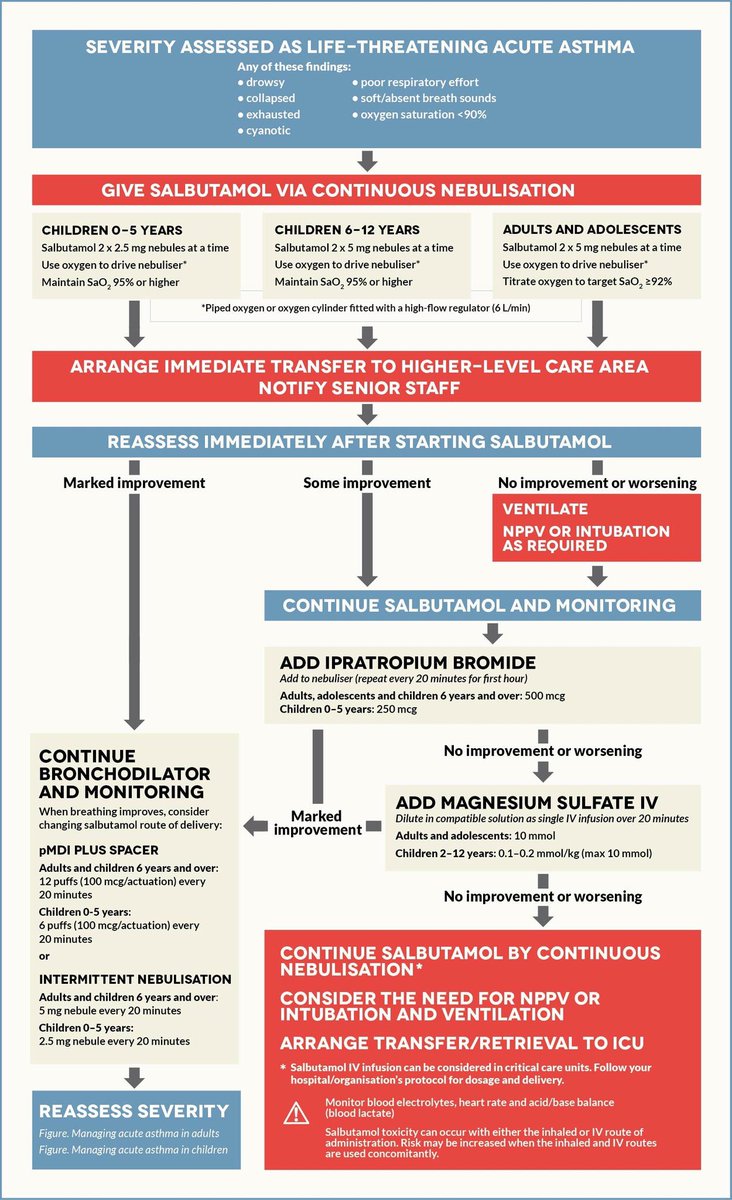

🔴ثامنًا: ايش هي الخطه العلاجيه بالترتيب :

مريض ربو حاد acute:

اولا: اذا جاك مريض ازما في حاله حرجه

يعني acute asthma تعطيهsupportive care

الي يحتاجه مع ادوية SABA مثل salbutamolمع اوكسجين على طريقة:

(back to back)

يعني كل20د تجدد الين يرد طبيعي

تابع👇

مريض ربو حاد acute:

اولا: اذا جاك مريض ازما في حاله حرجه

يعني acute asthma تعطيهsupportive care

الي يحتاجه مع ادوية SABA مثل salbutamolمع اوكسجين على طريقة:

(back to back)

يعني كل20د تجدد الين يرد طبيعي

تابع👇